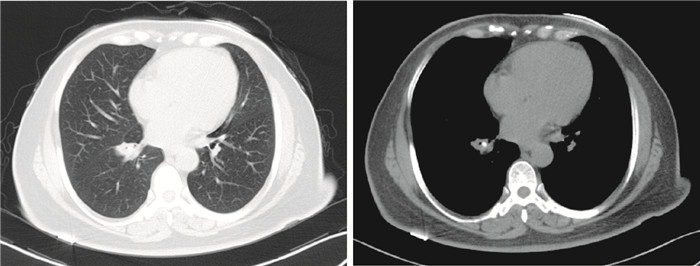

病例3??患者男性,64歲,司機,因“干咳、氣促1個月”入院。患者1個月前無明顯誘因下出現咳嗽,呈陣發性,干咳為主,咳嗽劇烈時伴有氣促,無發熱、乏力、盜汗、咯血、胸悶、胸痛等癥狀。肺動脈CT血管成像提示右肺中下葉支氣管不規則,右肺下葉支氣管管腔內致密灶,兩肺氣腫,肺血管未見明顯異常(圖 11)。否認吸煙、酗酒史,否認家族性遺傳病史。入院時查體:神清,精神可,步入病房,皮膚鞏膜無黃染,淺表淋巴結未觸及腫大,氣管居中,口唇無發紺,雙肺呼吸音清,未及干濕啰音,心、腹查體未見異常,雙下肢未見水腫,未見杵狀指(趾)。入院初步診斷:右側支氣管內異物可能。